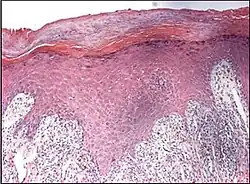

Psoriaform dermatitis typically displays:[2]

- Regular epidermal hyperplasia, elongation of the rete ridges, hyperkeratosis, and parakeratosis.

- Usually:A superficial perivascular inflammatory infiltrate

- Often: Thinning of epidermal cells overlying the tips of dermal papillae (suprapapillary plates), and dilated, tortuous blood vessels within these papillae

| Psoriasis | Present | Diffuse | Regular | Thin | Decreased or absent | Increased mitoses; minimal spongiosis Clubbed rete pegs[12][13] |

Absent |

|

| |